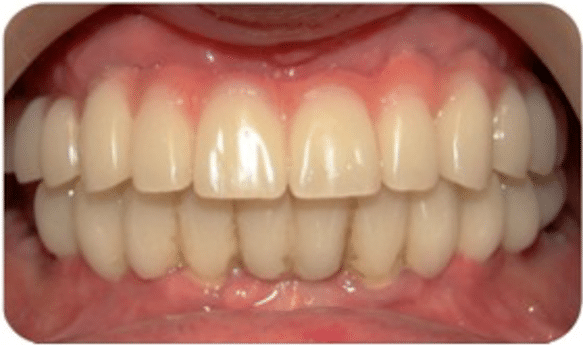

- L’esthétique : une prothèse dentaire posée sur un implant offre le meilleur résultat esthétique par rapport à une dent naturelle. Avec les têtes de couronnes en céramique, plus de risques de voir apparaître une «ligne grise» au bord de la gencive avec les années.